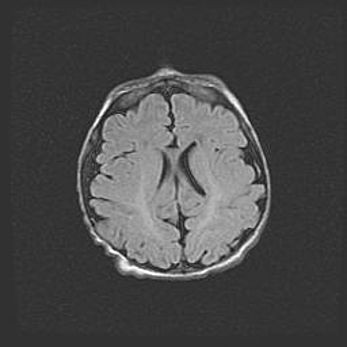

Сообщающаяся гидроцефалия. Кистозная энцефаломаляция головного мозга.

Возраст: 3 месяца 4 дня

Вес: 3100 г

Пол: женский

Окружность головы: 34 см

Срок гестации: 31 неделя

Кистозная энцефаломаляция головного мозга - одна из форм поражения головного мозга в детском возрасте. Характеризуется возникновением множественных и распространённых кист в коре, белом веществе и подкорковых образованиях головного мозга у плодов, новорождённых и детей раннего возраста. Развитие кистозной энцефаломаляции связано с внутриутробной асфиксией и гипотонией, родовой травмой, тромбозом синусов, пороками развития сосудов, инфекциями, сепсисом и другими причинами. Наиболее значимые инфекционные агенты: вирусы простого герпеса, цитомегалии, краснухи, токсоплазмы, энтеробактерии, золотистый стафилококк и другие.